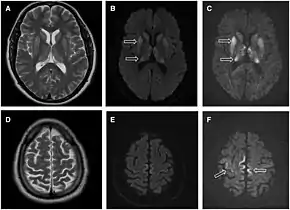

Imaging

Imaging of the brain may be performed during medical evaluation, both to rule out other causes and to obtain supportive evidence for diagnosis. Imaging findings are variable in their appearance, and also variable in sensitivity and specificity.[43] While imaging plays a lesser role in diagnosis of CJD,[44] characteristic findings on brain MRI in some cases may precede onset of clinical manifestations.[45]

Brain MRI is the most useful imaging modality for changes related to CJD. Of the MRI sequences, diffuse-weighted imaging sequences are most sensitive.[46] Characteristic findings are as follows:

- Focal or diffuse diffusion-restriction involving the cerebral cortex and/or basal ganglia. In about 24% of cases DWI shows only cortical hyperintensity; in 68%, cortical and subcortical abnormalities; and in 5%, only subcortical anomalies.[47] The most iconic and striking cortical abnormality has been called "cortical ribboning" or "cortical ribbon sign" due to hyperintensities resembling ribbons appearing in the cortex on MRI.[48] The involvement of the thalamus can be found in sCJD, is even stronger and constant in vCJD.[49]

- Varying degree of symmetric T2 hyperintense signal changes in the basal ganglia (i.e., caudate and putamen), and to a lesser extent globus pallidus and occipital cortex.[44]

- Cerebellar atrophy

Brain FDG PET-CT tends to be markedly abnormal, and is increasingly used in the investigation of dementias.

- Patients with CJD will normally have hypometabolism on FDG PET.[50]